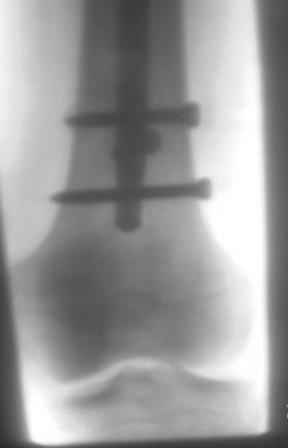

Уважаемый Абдурашид! Штифт у Вас по-видимому MetaDiaFix-F ЦИТОвский? Если так, то по снимку проксимального конца бедра видно, что в динамическом отверстии винт проведен у дистального края.Разрешите мои сомнения. Если это так,то это статический вариант. Запаса на динамизацию в дистальном овальном отверстии не хватит. Я бы оставил как есть. Бедро как правило хорошо срастается. Если будут проблемы - лучше проксимально переблокировать в динамический вариант после появления признаков Rg мозоли. Удачи! С уважением Станислав Дмитриев.

Уважаемый Станислав, штифты действительно ЦИТОвские- ВНПБ (для высоких и низких переломов бедра), Вы правильно заметили , что в проксимальном овальном винт проведен статистическим варианте, а в дистальном у середины овального отверстия, что запаса на динамизацию не хватить., и мне понравился Ваша идея проксимально переблокировать в динамический вариант! так как можно и без ЭОПа и при помощи кондуктора.

Уважаемый Абдурашид! У нас есть опыт "замены" винтов без проксимального кондуктора. По точке рубца соответствующего винта ищем головку его отверткой. Плотно вставляем в шлиц(если необходимо - "освобождаем" шлиц от рубцов)и затем строго параллельно отвертке сверлим отверстие у проксимального края. Вводим "динамический" винт, а остальные проксимальные убираем. Как правило всегда получается. Можно и с кондуктором. Удачи!